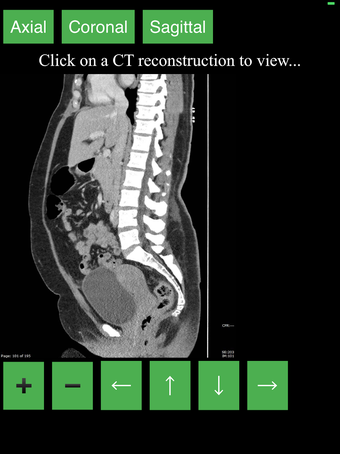

هذا تطبيق فريد من نوعه، تم تطويره من قبل مجموعتنا، لغرض توفير طريقة بسيطة ومفيدة لتعلم تشريح الجسم بالمقطع العرضي.

نقدم أفضل طريقة لتعلم هذا الموضوع، باستخدام جهاز تصوير تشخيصي (CT). نحن نحاول جعل عملية التعلم سهلة وممتعة قدر الإمكان، باستخدام نموذج ثلاثي الأبعاد للجسم البشري.

ما هو CT؟

هذا نوع من التصوير الذي يستخدم أشعة الأشعة السينية لعرض داخل الجسم وبناء صورة للأعضاء والعظام. هذا مفيد للكشف عن الأمراض والإصابات، وأيضًا لمساعدة في فهم تشريح الجسم.